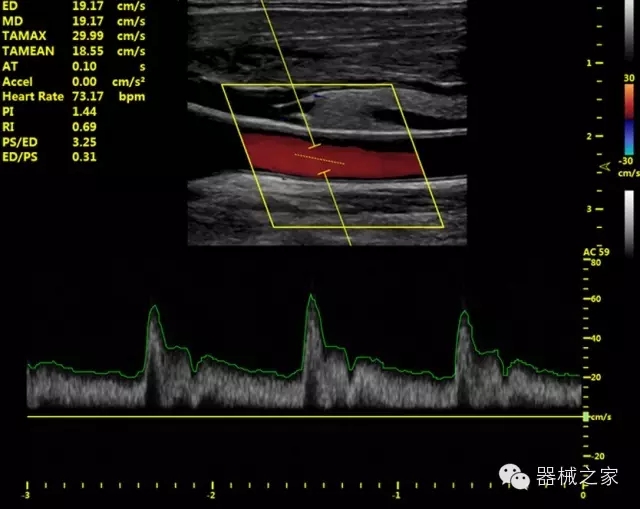

·獨(dú)有的HoloTM PW 實(shí)時(shí)3取樣門PW成像技術(shù),精確進(jìn)行血管診斷;

·一鍵優(yōu)化B、Color、PW,Auto Doppler自動(dòng)識(shí)別血管位置、偏轉(zhuǎn)角度等,提高工作效率;

·30°超廣角精細(xì)偏轉(zhuǎn)成像技術(shù),更優(yōu)異的頻譜圖像;